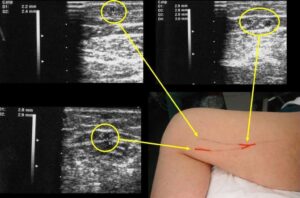

- Δοπλερογραφία Άνω Άκρου (Upper Extremity Doppler Ultrasound): Η δοπλερογραφία χρησιμοποιεί τις ήχο κύματα για να εξετάσει τη ροή του αίματος μέσα στα αγγεία. Αυτή η εξέταση μπορεί να βοηθήσει στην αξιολόγηση της παροχής αίματος και στον εντοπισμό ενδεχόμενων αγγειακών παθήσεων.

- Εικονολογική Εξέταση με Χρήση Υπερήχων (Ultrasound Imaging): Οι υπερήχοι μπορούν να χρησιμοποιηθούν για να παράγουν εικόνες των αγγείων και να αξιολογήσουν τη ροή του αίματος. Είναι μια μη επεμβατική μέθοδος και ευαίσθητη για τον εντοπισμό αγγειακών προβλημάτων.

- Δοπλερογραφία (Doppler Ultrasound): Η δοπλερογραφία χρησιμοποιεί τον ήχο για να αξιολογήσει τη ροή του αίματος μέσα στις αρτηρίες και να εντοπίσει ενδεχόμενες στενώσεις ή προβλήματα με τη ροή.

- Υπερήχοι Αρτηριών (Arterial Ultrasound): Είναι μια εξέταση που χρησιμοποιεί υπερήχους για την παραγωγή εικόνων των αρτηριών. Χρησιμοποιείται για τον έλεγχο του διαμετρήματος των αρτηριών, τον εντοπισμό αθηρωματικών πλακών και άλλων ανωμαλιών.

Το Έγχρωμο Υπερηχογράφημα Αγγείων, επίσης γνωστό ως Colored Ultrasound Duplex Scan, είναι μια εξέταση που συνδυάζει δύο τεχνικές υπερήχων για τον έλεγχο των αγγείων: τη δοπλερογραφία και την αντιδραστική (duplex) υπερηχογραφία. Αυτή η εξέταση παρέχει λεπτομερείς εικόνες της ανατομίας των αγγείων και πληροφορίες σχετικά με τη ροή του αίματος μέσα σε αυτά.

Το Έγχρωμο Υπερηχογράφημα Αγγείων, επίσης γνωστό ως Colored Ultrasound Duplex Scan, είναι μια εξέταση που συνδυάζει δύο τεχνικές υπερήχων για τον έλεγχο των αγγείων: τη δοπλερογραφία και την αντιδραστική (duplex) υπερηχογραφία. Αυτή η εξέταση παρέχει λεπτομερείς εικόνες της ανατομίας των αγγείων και πληροφορίες σχετικά με τη ροή του αίματος μέσα σε αυτά.

Η δοπλερογραφία χρησιμοποιεί ήχο κύματα για να αξιολογήσει την ταχύτητα της ροής του αίματος σε ένα αγγείο. Αυτή η τεχνική είναι χρήσιμη για τον εντοπισμό στενώσεων ή αποφραγμάτων στις αρτηρίες και τις φλέβες. Τα χρώματα στην εικόνα αντιπροσωπεύουν την κατεύθυνση και την ταχύτητα της ροής.

Η αντιδραστική υπερηχογραφία (duplex ultrasound) παρέχει δομικές εικόνες των αγγείων, όπως οι εικόνες που λαμβάνονται με την κανονική υπερηχογραφία. Σε συνδυασμό με τη δοπλερογραφία, είναι δυνατό να διακριθούν οι αρτηρίες από τις φλέβες και να αξιολογηθεί η ροή του αίματος.

Αυτή η μέθοδος χρησιμοποιείται ευρέως για την αξιολόγηση της κατάστασης των αγγείων, συμπεριλαμβανομένων των αρτηριών και των φλεβών, και μπορεί να χρησιμοποιηθεί σε διάφορα μέρη του σώματος, όπως τα άνω και κάτω άκρα, ο λαιμός, ο κορμός, και άλλες περιοχές.